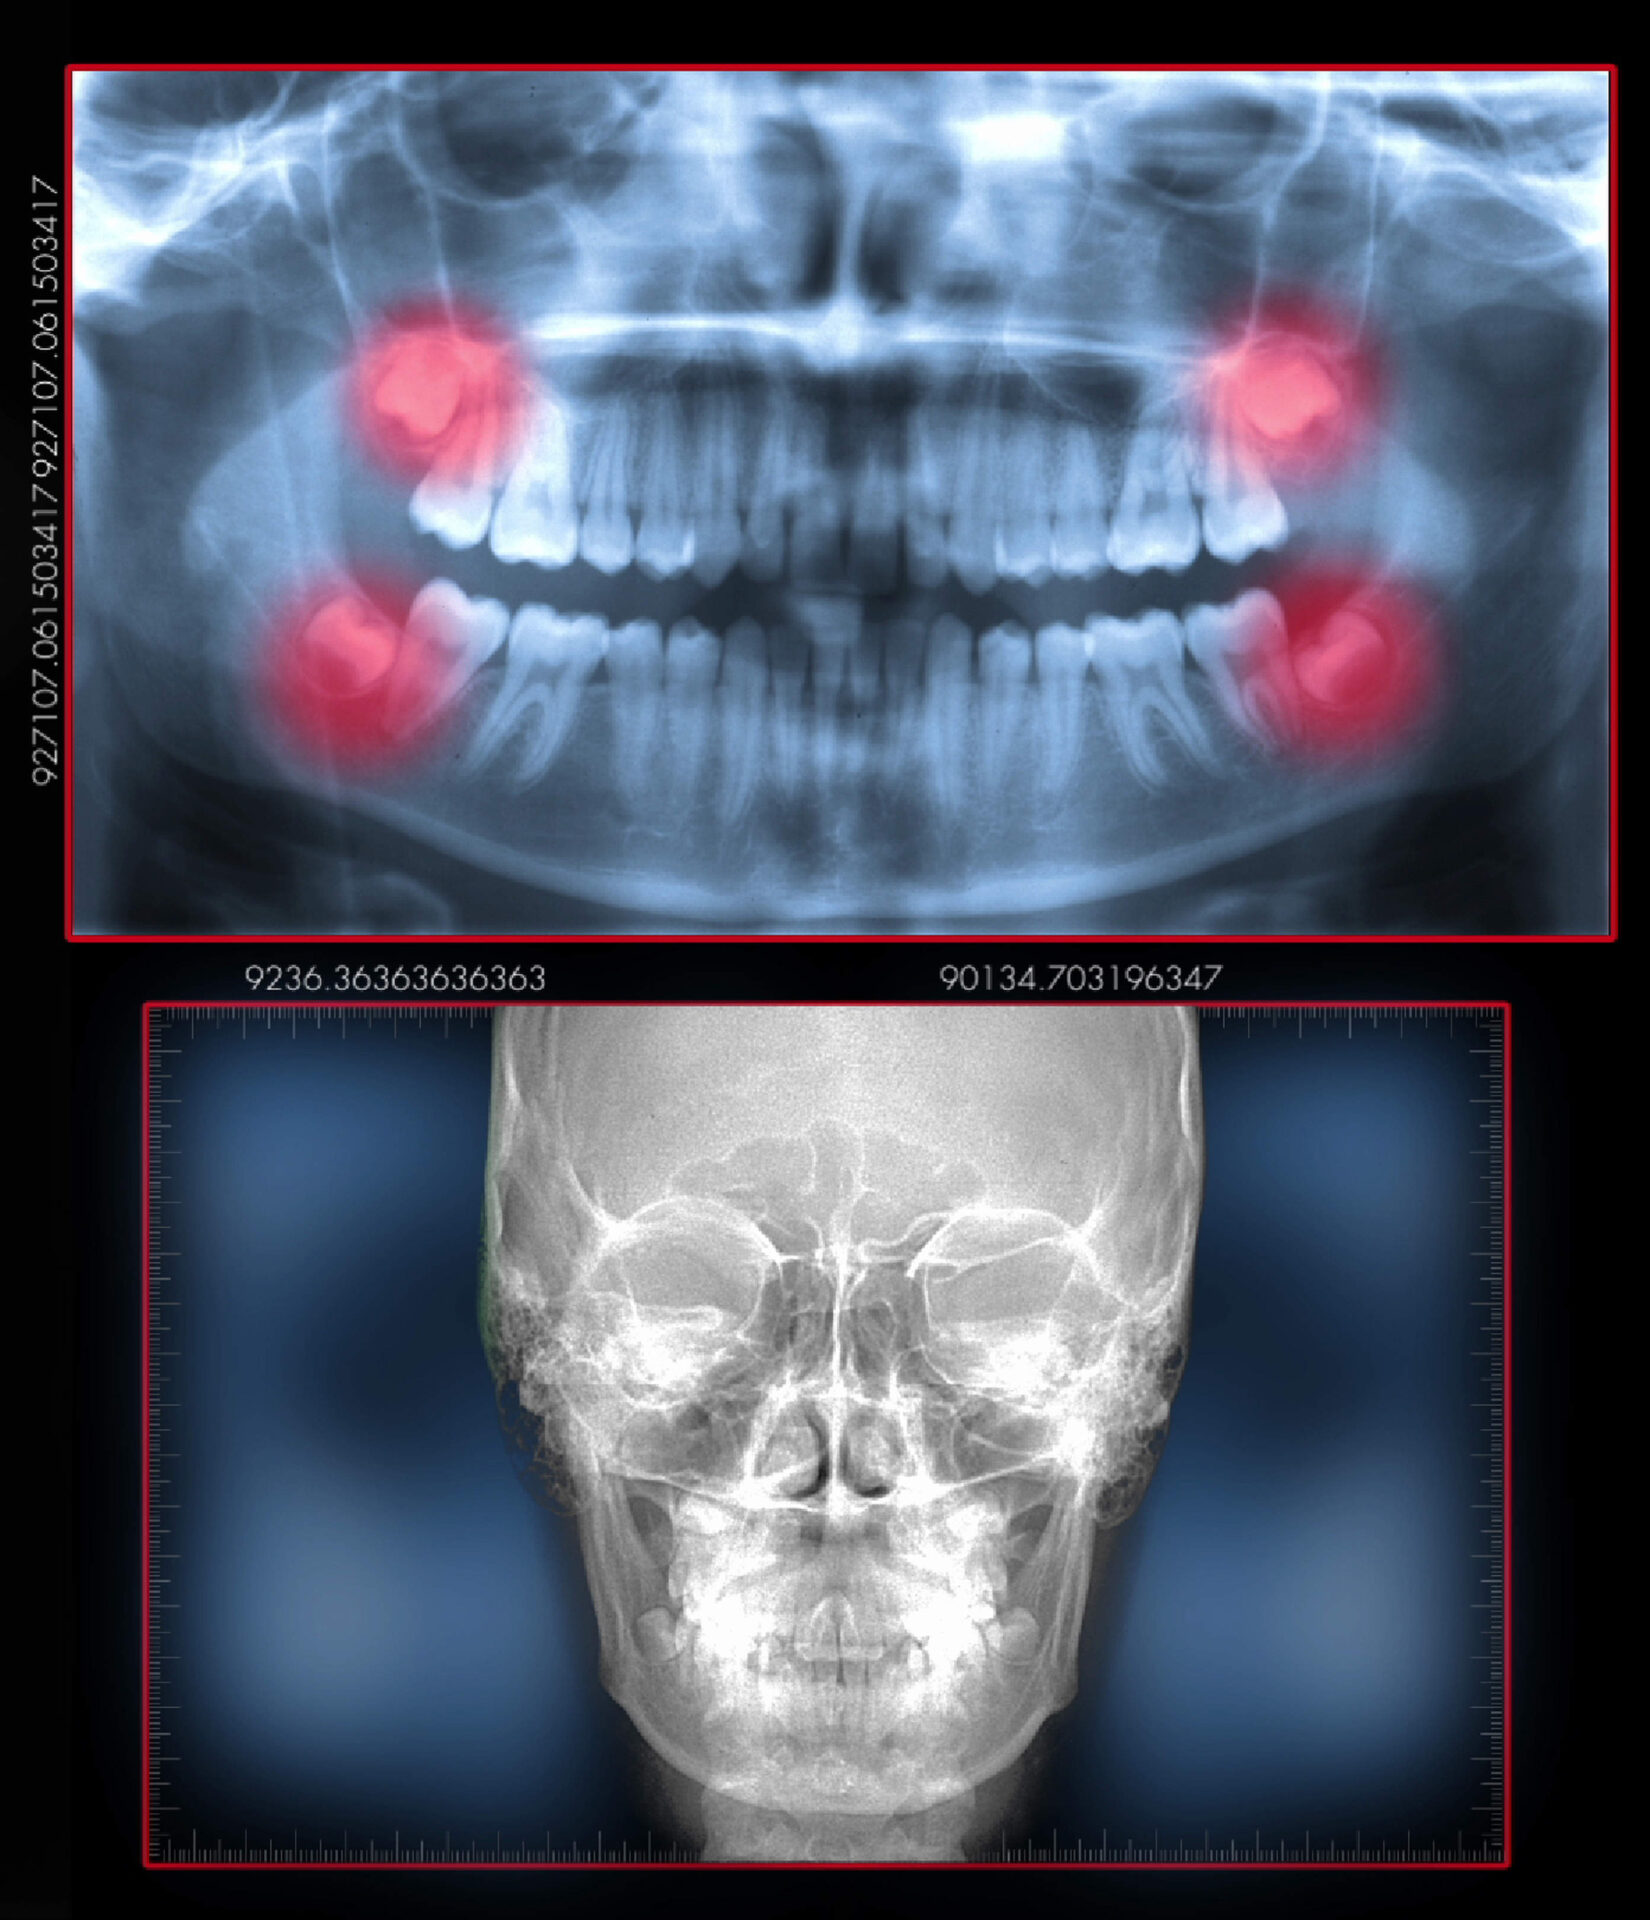

Para diagnosticar corretamente a ATM, o profissional irá realizar um exame minucioso da musculatura e tecidos da cabeça e pescoço, além da solicitação de exames radiográficos. Os sinais e sintomas são fundamentais para o fechamento do diagnóstico.

Após exame rigoroso e exames complementares (rx, ressonaria magnética,tomografia, polissonografia, exames de sangue, etc), é estabelecido um plano de tratamento.